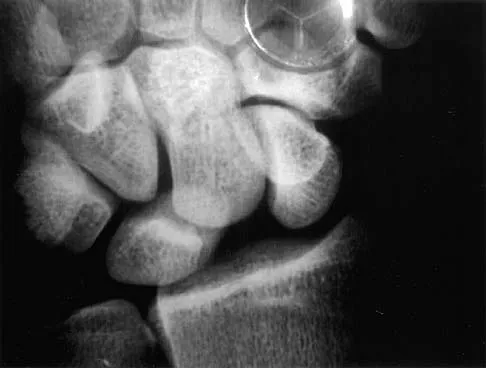

A 23-year-old woman sustains an injury to her right hand after falling off her snowboard. Examination reveals that she has difficulty moving her fingers. A radiograph and a clinical photograph are shown in Figures 8a and Figure 8b. Management should consist of

Explanation

The radiograph reveals oblique fractures of the third and fourth metacarpals. The rotational component of the fracture displacement is well visualized on the clinical photograph, which shows scissoring of the middle finger over the ring finger. The fracture obliquity results in rotational deformity that cannot be adequately maintained and held by closed treatment. The treatment of choice is open reduction and internal fixation. Stern PJ: Fractures of the metacarpals and phalanges, in Green DP, Hotchkiss RN, Pederson WC (eds): Green's Operative Hand Surgery, ed 4. Philadelphia, PA, 1999, pp 711-771. Freeland AE, Benoist LA, Melancon KP: Parallel miniature screw fixation of spiral and long oblique hand phalangeal fractures. Orthopedics 1994;17:199-200.